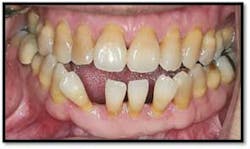

Charting shows that all pockets are now generalized 1-3 mm with no BOP

The patient is thrilled with her outcome and now has a stable dentition.

She is ready to move forward with orthodontia and will continue with periodontal supportive therapy every 3 months.